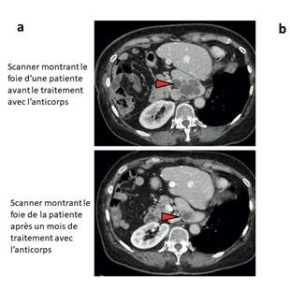

Les freins majeurs dans la prise en charge de patients atteints d’un cancer sont la résistance aux traitements anticancéreux et la baisse de la sensibilité aux chimiothérapies. Une équipe dirigée par un chercheur du CNRS1 a étudié pour la première fois l’inhibition d’une protéine responsable de ces phénomènes par un anticorps. Il permet, non seulement lorsqu’il est utilisé seul de stabiliser la maladie, voire même de réduire les métastases, et lorsqu’il est combiné avec des chimiothérapies, il améliore les résultats de ces traitements conventionnels pour certains cancers. Obtenus chez la souris et l’humain, ces résultats sont publiés dans deux articles de Nature le 2 août 2023. Différents essais cliniques de phase II sont actuellement en cours, les résultats seront connus d’ici la fin de l’année 2024.